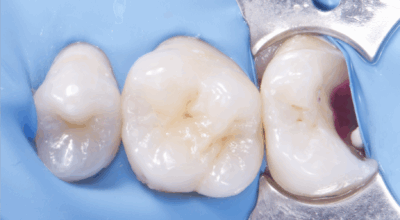

Cas clinique

Coiffage pulpaire direct : 90,4% de taux de succès